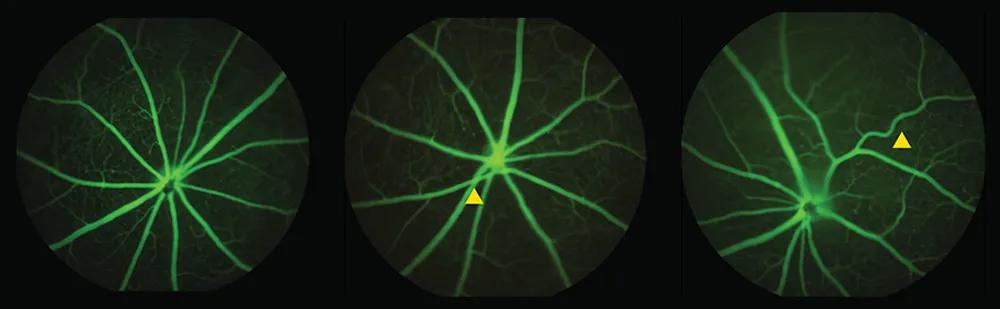

The team studied mice with a mutation called MTHFR677C>T, which is found in up to 40% of people. They found that the mice’s retinas had twisted vessels, narrowed and swollen arteries, and less vessel branching as early as six months of age. This reflects similar changes in the brain linked to poor blood flow and increased risk of cognitive decline. Vessels that appear more twisted and looped than normal can signal problems with hypertension, as the narrowing tissue limits nutrient and oxygen transport, Reagan said.

“We can see these wavy vessels in the retinas, which can occur in people with dementia,” Reagan said. “That speaks to a more systemic problem, not just a brain- or retina-specific problem. It could be a blood pressure problem affecting everything.”

For example, the study also captured the influence of sex and age, with female mice showing worse outcomes. By 12 months, they showed reduced vessel density and branching, highlighting progressive vascular changes. Similarly, women develop dementia more often than men, according to the World Health Organization.